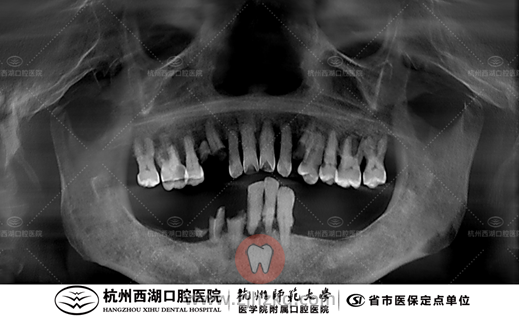

术前CBCT照如下